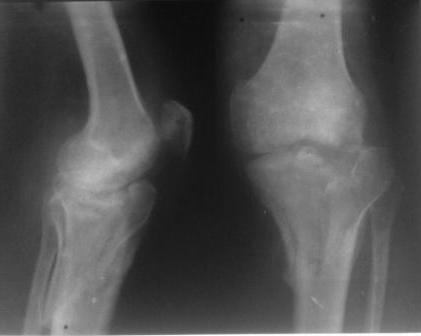

Застарелый перелом 41С3

Обратился больной 46л. 3-месяца назад в каком-то городке Дальнего Востока упал с высоты, сделана Р-графия, наложена гипсовая повязка, от предложенной операции отказался и уехал домой, дальше где и как лечился, не говорит.

Ходит при помощи двух костылей, жалобы на боли при нагрузке, в покое и при движении, без нагрузке боли нет, разгибание 175 гр, сгибание 90 гр, симптомов повреждения связочного аппарата к/с не определяется, от предложенного артродеза пока отказывается.

Уважаемые коллеги! какие будут мнения по поводу лечения, эндопротез недоступен. Заранее благодарю! С уважением Абдурашид.